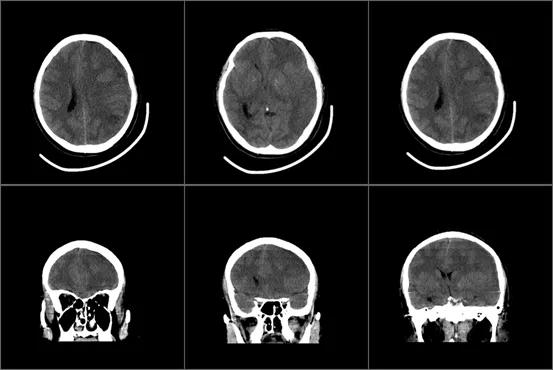

转至重症监护室抢救,梁还是没有脱离危险,几位外科专家打开电脑上的影像,这是梁急查的颅脑CT。

医生指了指几处明显有异常的位置,告诉我说梁的左侧脑组织肿胀,中线偏移,左侧侧脑室受压,考虑颅内感染继发脑组织肿胀,脑疝形成,有做去骨瓣减压术的指征。